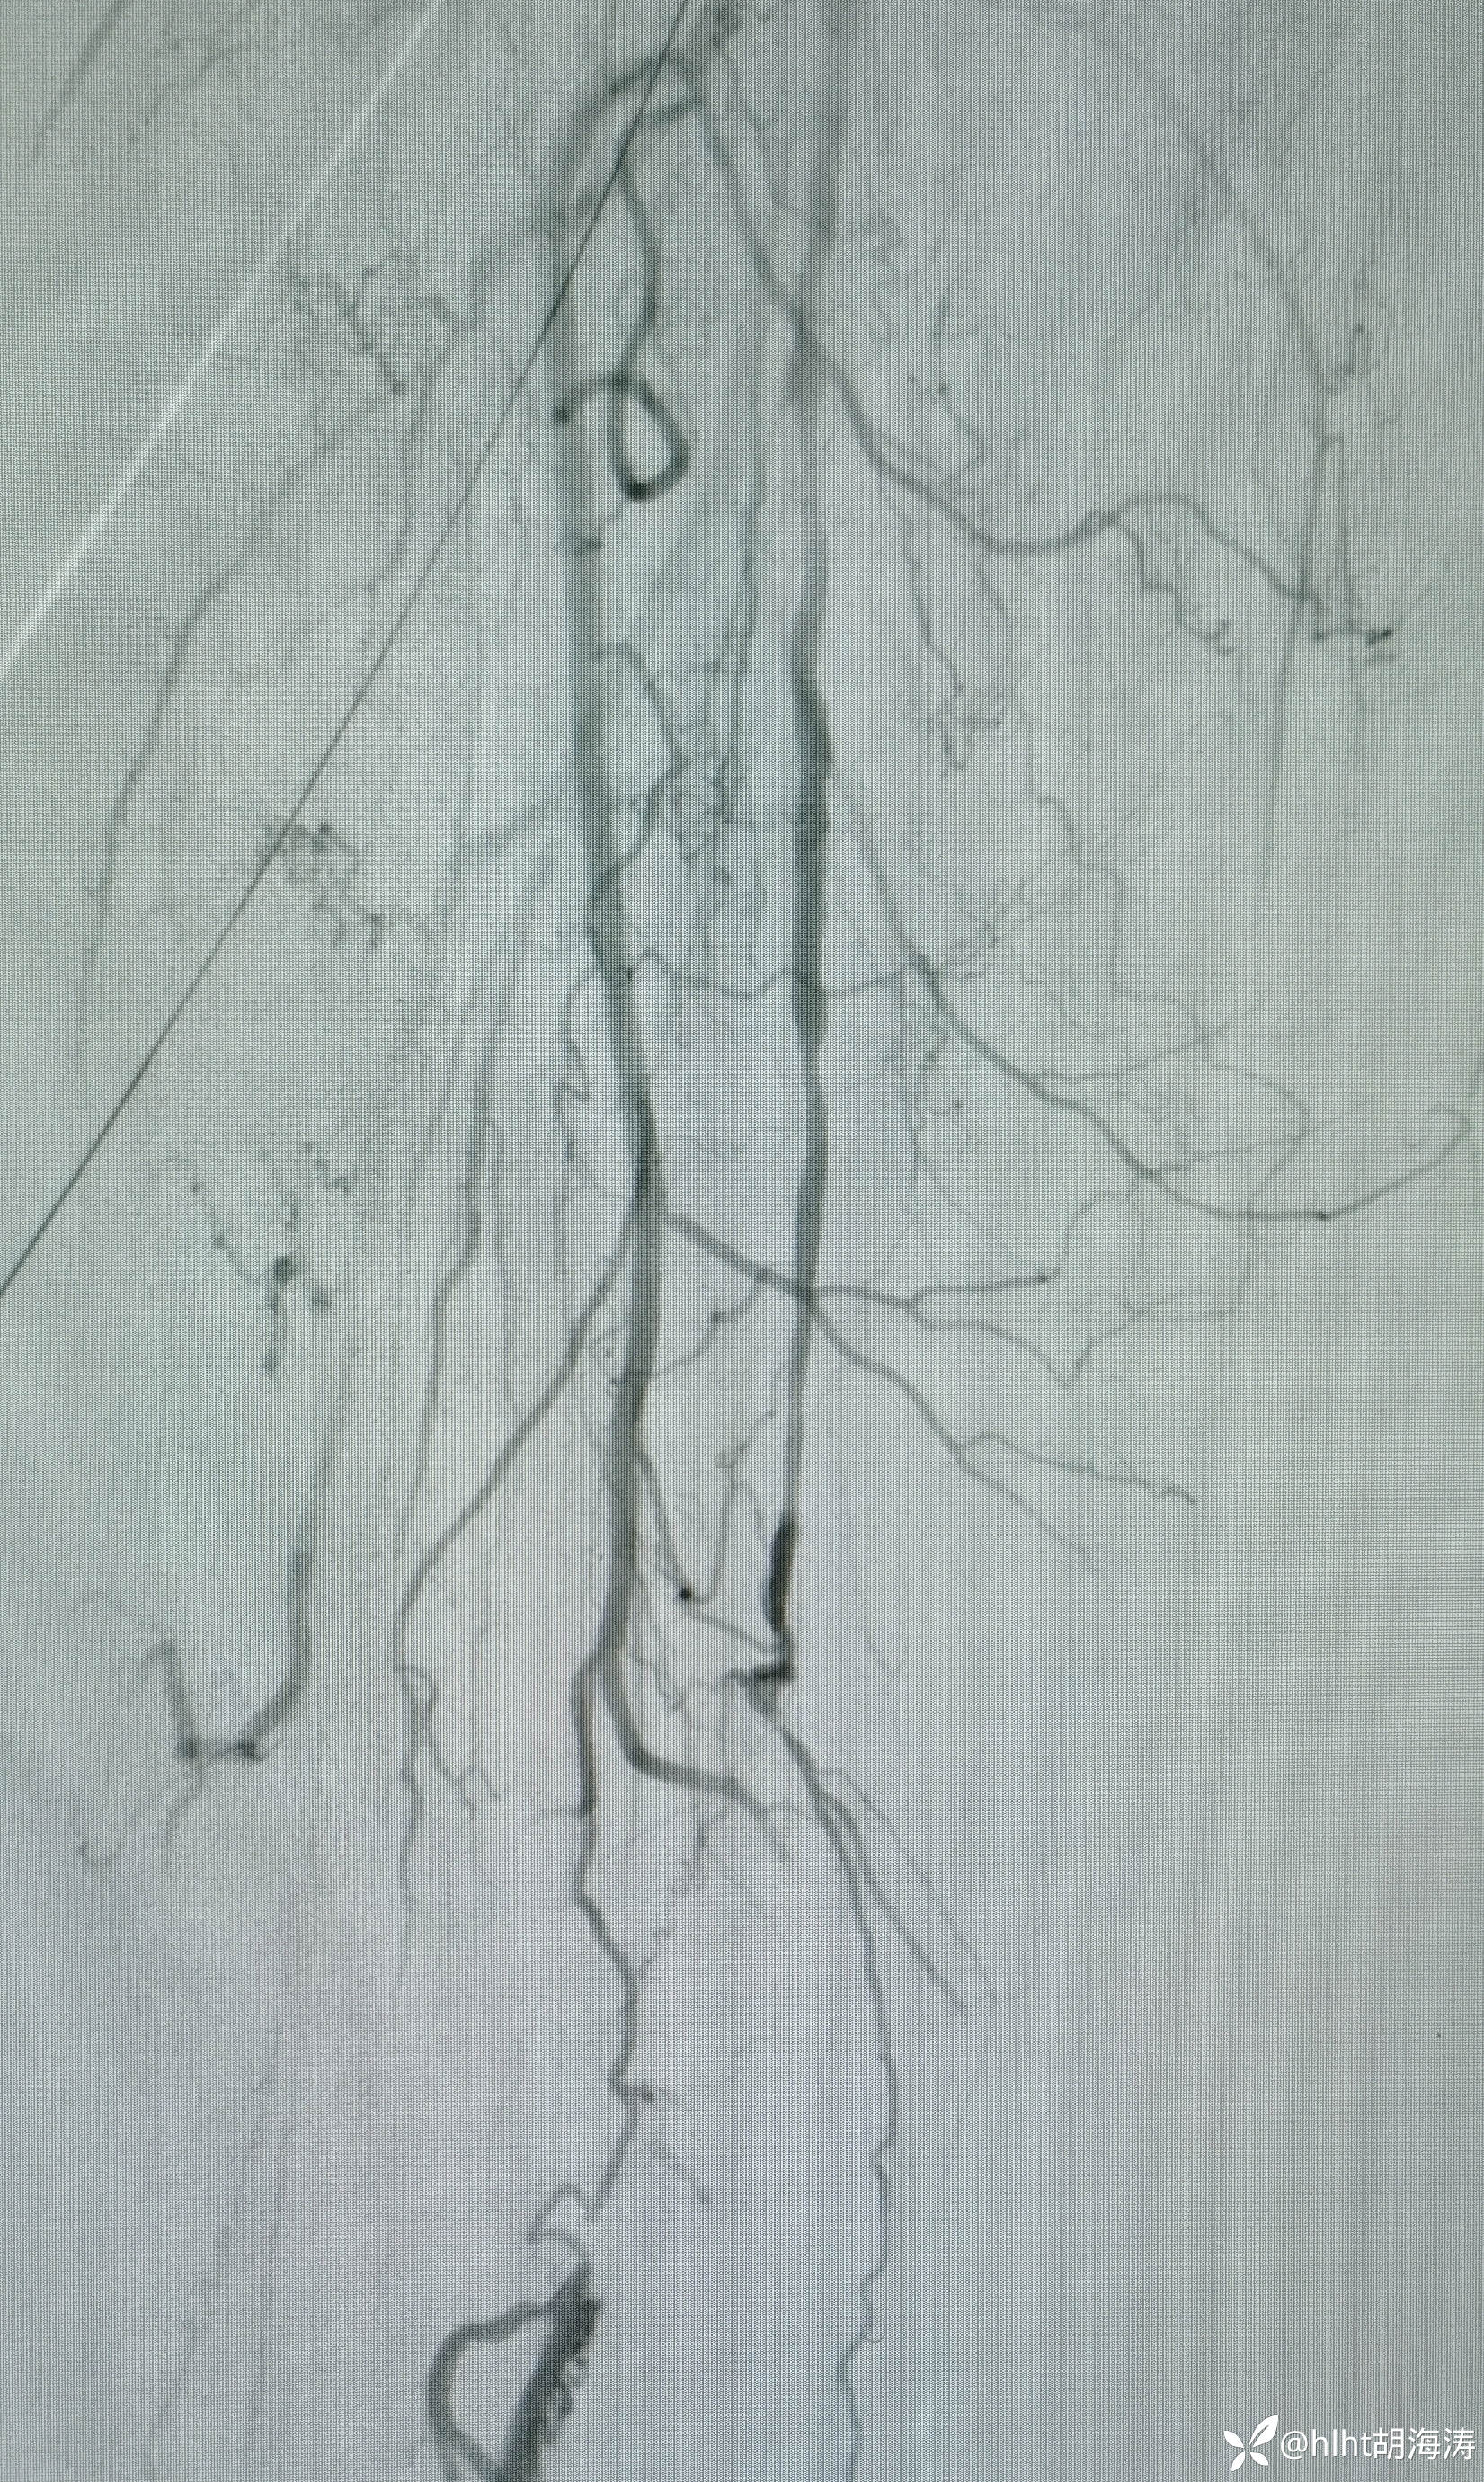

手术结束时,左侧下肢远端造影,很通畅:

23:00手术结束,双侧腹股沟区股动脉恢复搏动,右侧股浅闭塞段没法打通,侧枝循环好,手术顺利;